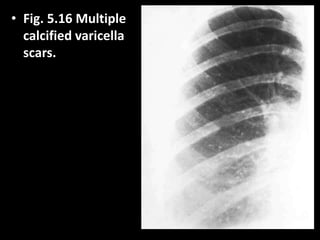

• Fig. 5.16 Multiple

calcified varicella

scars.

• Fig. 5.16Multiple calcified varicella scars.